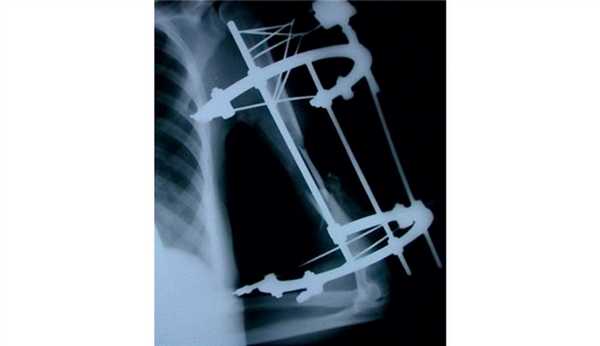

Кровоснабжаемый трансплантат из малоберцовой кости использовался у 38 (93%) пациентов, васкуляризованный трансплантат из медиального мыщелка бедренной кости — у 3 (7%) пациентов (рис. 1). Рис. 1. Распределение пациентов по типу васкуляризованного трансплантата.

Во всех случаях применялся накостный остеосинтез пластиной без контакта пластины с трансплантатом (мостовидная костная пластика).

Консолидация перелома при кровоснабжаемой костной пластике была достигнута в 36 (88%) случаях в течение 4-6 мес (рис. 2): Рис. 2. Результаты оперативного лечения с использованием кровоснабжаемой костной пластикой. в группе применения малоберцового трансплантата консолидация была достигнута в 33 случаях, в группе трансплантата из мыщелка бедренной кости — в 3 случаях.

На рис. 3-9 Рис. 3. Пациентка И., 34 лет. Внешний вид до операции. Рис. 9. Внешний вид и функция через год после операции. представлены все этапы обследования и лечения пациентки И.

Рис. 4. Рентгенограмма пациентки И. до операции.

Рис. 5. Пациентка И. Этапное оперативное вмешательство. а — замещение дефекта плечевой кости цементным спейсером; б — транспозиция торакодорсального лоскута в область мягкотканного дефекта плеча; в — послеоперационная рентгенограмма.

Рис. 6. Рентгенограммы пациентки И. после удаления цементного спейсера.

Рис. 7. Оперативное лечение пациентки И.: пластика левой плечевой кости свободным кровоснабжаемым трансплантатом из малоберцовой кости.